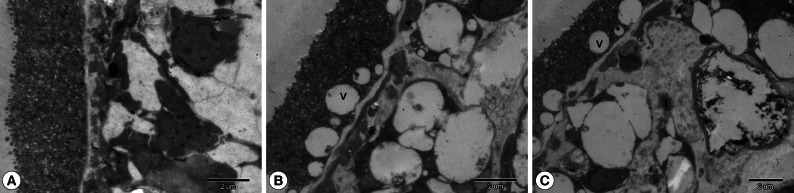

To visualize the structural alterations in protoscolices imposed by SB202190 treatment, parasites were processed for scanning (SEM) and transmission electron microscopy (TEM) after the initiation of treatment with 40 µM SB202190. Control cultures exhibited no ultrastructural alterations in parasite tissue during the whole incubation period (Figs. 2A, 3A). In contrast, morphological and ultrastructural damages were detected in treated protoscolices. At day 3 post-incubation, observations by SEM and TEM of protoscolices incubated with SB202190 revealed the ultrastructural changes. The ultrastructural changes included tegumental alterations (Fig. 2B), rostellar disorganization, loss of hooks, and shedding of microtriches of the scolex region (Fig. 2C). In some protoscolices, loss of morphology was evident (Fig. 2D). Ultrastructural studies by TEM revealed severely affected internal tissues, resulting in loss of its integrity, an increase in the number of lipid droplets, and an increase of vacuoles (Fig. 3B, C).

SB202190 is a pyridinyl imidazole derivative and is known to be a specific inhibitor of p38 MAPK. In line with these studies, we have proved that SB202190 is effective in inactivating in vitro cultured E. granulosus protoscolices. Moreover, the increased effectiveness was induced proportionally with increased concentrations of SB202190. Protoscolices cultured with 80 µM SB202190 were killed considerably faster than protoscolices cultured with 40 µM, 20 µM, and 10 µM SB202190. After 1 day of exposure to 80 µM SB202190, viability was approximately 30%, and it was reduced to 5% after 4 days of incubation. As demonstrated in our experiments, the incubation of drug produced ultrastructural alterations with tegumental alterations, rostellar disorganization, and loss of hooks, and the internal tissue was severely affected. In vitro SB202190 did show some potential as a scolicidal agent for inactivation of the hydatid cyst.

Fig. 3

Transmission electron microscopy of E. granulosus protoscolices treated with DMSO (A) or 40 µM SB202190 (B, C) for a period of 3 days. Note the presence of vacuoles (v) and lipid droplets (l).

Fig. 3 Transmission electron microscopy of E. granulosus protoscolices treated with DMSO (A) or 40 µM SB202190 (B, C) for a period of 3 days. Note the presence of vacuoles (v) and lipid droplets (l).